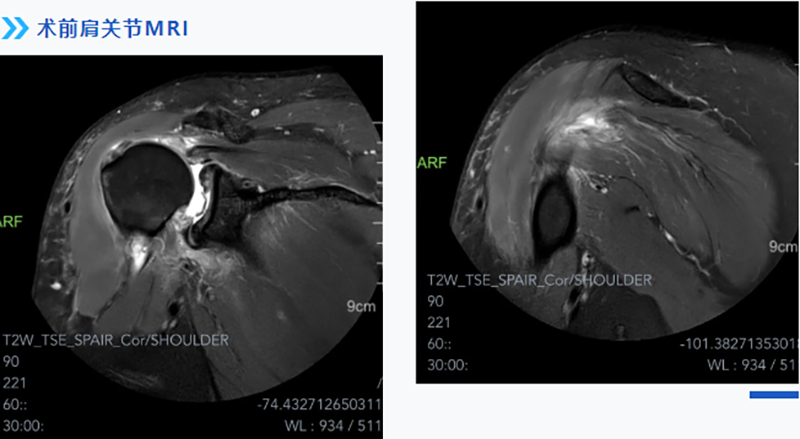

經過多方打聽,張師傅慕名來到柳州市人民醫院運動醫學科就診。運動醫學科主任韋釗嵐博士結合患者實際情況,仔細查體及閱片后給出了明確診斷:巨大肩袖撕裂,腋神經損傷(后上型巨大肩袖撕裂回縮導致神經牽拉)。

醫生介紹,肩袖主要由岡上肌、岡下肌、肩胛下肌及小圓肌組成。巨大肩袖撕裂一般指撕裂直徑大于5cm或撕裂的范圍波及2根以上的肩袖。因為撕裂范圍大,受累肌肉多,無論從手術方案制定還是手術技術難度上均是肩袖手術中最具挑戰的,特別是對多部分軟組織進行組織松解和調節平衡。